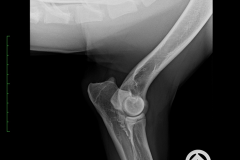

HD ZW: kW25/02 „69“ Größen-ZW: kW25/02 „101!